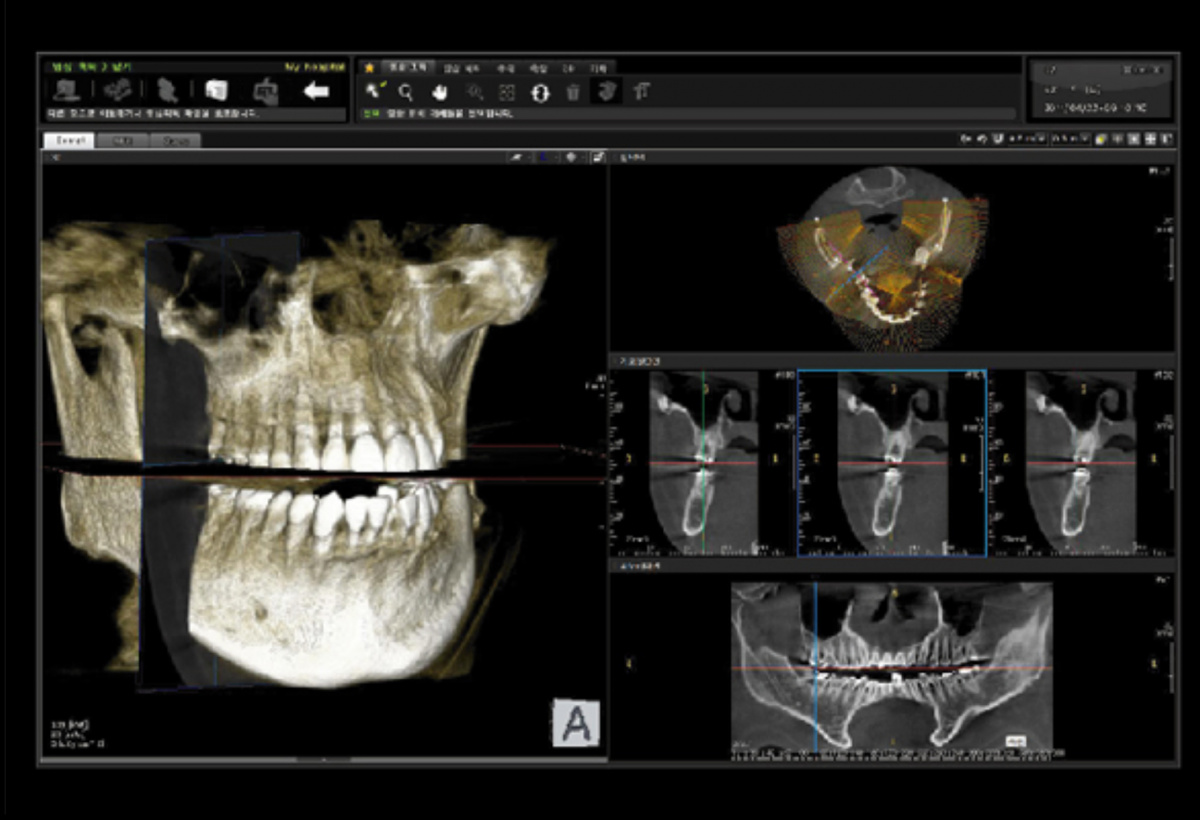

Немаловажным, а может главным вопросом, является универсальность программы-просмотровщика, в которой будут работать врачи-стоматологи. У Papaya 3D есть два варианта программ: Triana и OnDemand3D. Оба просмотровщика обладают схожим интерфейсом и имеют самые важные опции, а именно:

Triana.jpg  OnDemand3D.jpg

• режим MPR (многоплоскостная реконструкция). Именно здесь выстраивается интересующий участок челюсти или зуба для анализа.

• панорамный реформат. Возможность постройки классической и сегментарной панорамы позволяет продемонстрировать план лечения пациенту, а также оценить расположение анатомических структур на боковых кросс-секциях.

• модуль дентальной имплантации. Возможность виртуальной установки дентального имплантата с анализом окружающей костной ткани. В библиотеке представлен широкий спектр имплантологических систем с индивидуальной прорисовкой имплантата.

• выделение нижнечелюстного канала позволяет продемонстрировать расположение важного анатомического образования и определить зону безопасности при проведении лечения.

• функции плотности, линейных измерений и угла – необходимы для получения полноценной информации для последующего лечения.

• 3D режим – показывает трехмерную модель челюсти с целью определения аномалий, деформация, а также визуализации виртуальных имплантатов.

triana3.jpg triana4.jpg triana5.jpg

OnDemand3D (1).jpg OnDemand3D (2).jpg OnDemand3D 1.jpg

Таким образом обе программы являются простыми в пользовании, но обладающими обширным спектром возможностей для диагностики любыми специалистами-стоматологами. В данные программы происходит загрузка классических файлов DICOM 3.0, которые являются общепринятым форматом записи данных пациента. Это важный момент, так как позволяют врачу, имеющему полную версию программы загружать даже сторонние исследования и просматривать их в этих программах. Простота в освоении этих программ позволяет даже специалисту, не работающему раннее с этими программами, быстро адаптироваться и получить качественную информацию. Возможность выгрузки STL-файла дополнительно создает возможность интегрировать данные с цифровым ортопедическим протоколом.